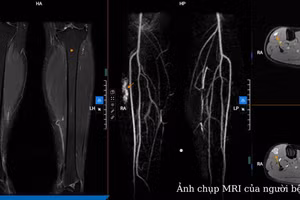

GDTĐ - Bệnh nhân 21 tuổi (ngụ quận Tân Phú) suýt chết do bị dị dạng mạch máu "khủng" ở ruột non hiếm gặp, gây xuất huyết ồ ạt.